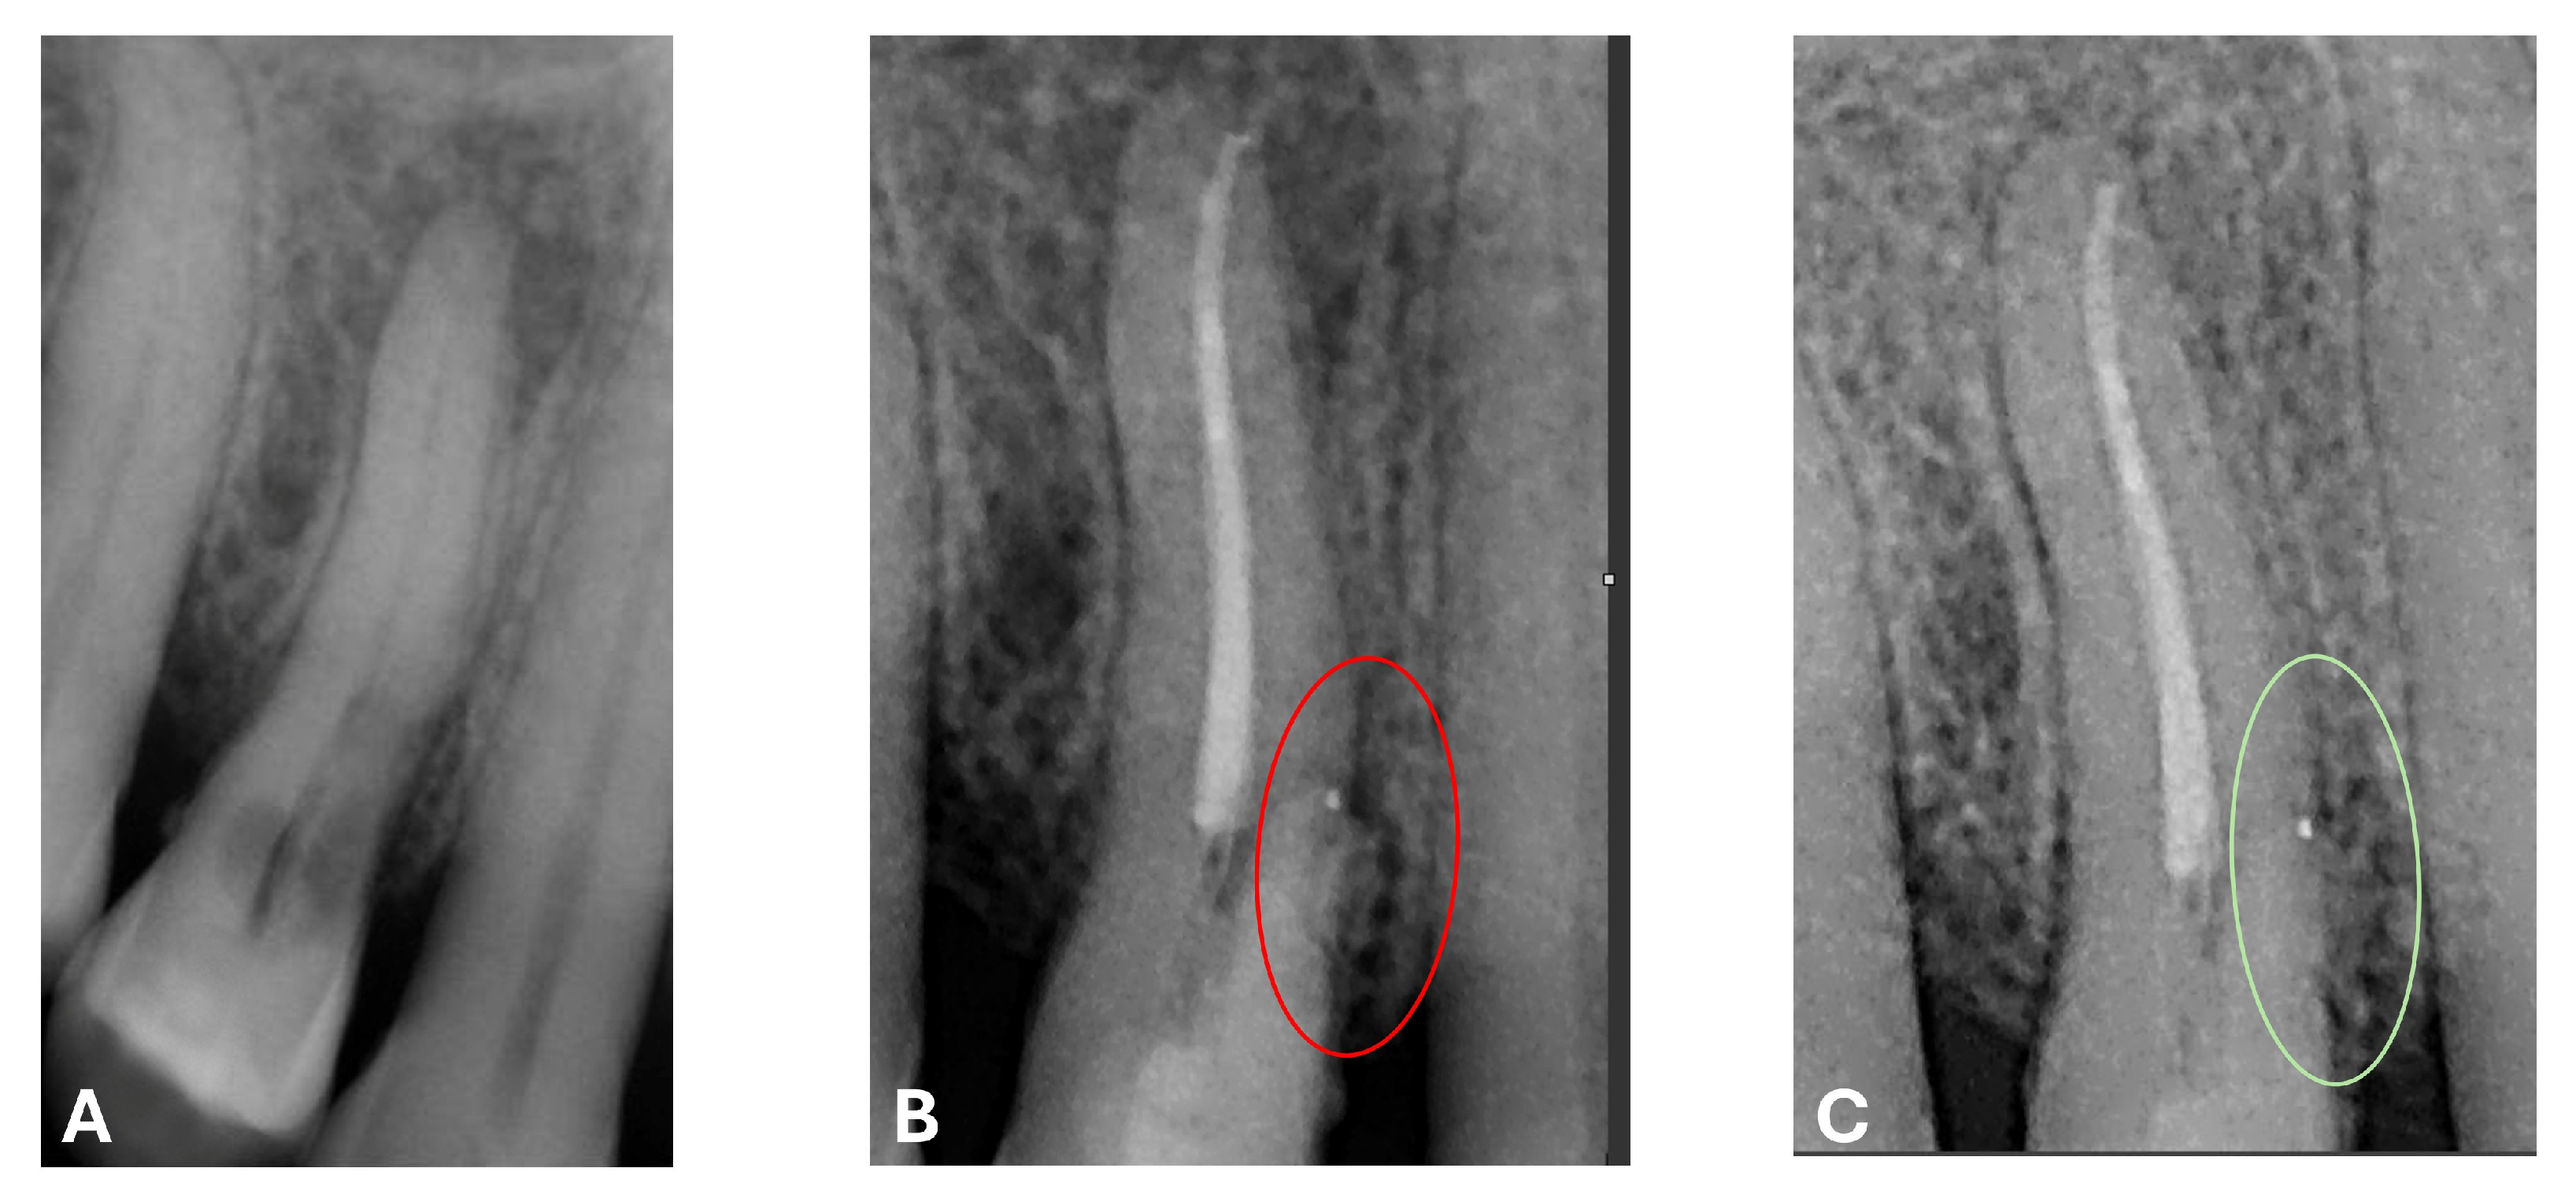

At the 12-month radiographic follow-up, healing of the EPL was confirmed. Restoration of the lamina dura and the periodontal ligament adjacent to the treated site was observed (Figure 16 and Figure 17).

Figure 17.

EPL before (A) and after treatment (red circle showing mesiocervical widening of the lamina dura space) (B) and at 12-month follow-up (C) with radiographic evidence of restoration of the lamina dura (green circle), periodontal ligament space and absence of PL.

In the present case report, a one-year follow-up is presented, demonstrating excellent progression of lesion healing, an increase in the height of the alveolar bone adjacent to the lamina dura, resolution of the pathological probing depth, recovery of the continuity of the periodontal ligament and lamina dura along the root surface and in correspondence with the previously affected area of the cervical resorption and lesion, and complete remission of odontogenic symptoms, restoring the functional integrity of the tooth [33]. Consequently, the efficacy of the treatment can be affirmed: through the use of bioceramic cements in two formulations and the implementation of a meticulously performed intraoperative endodontic technique, a successful therapeutic outcome was achieved, with the dental element remaining functional and in position within the arch.